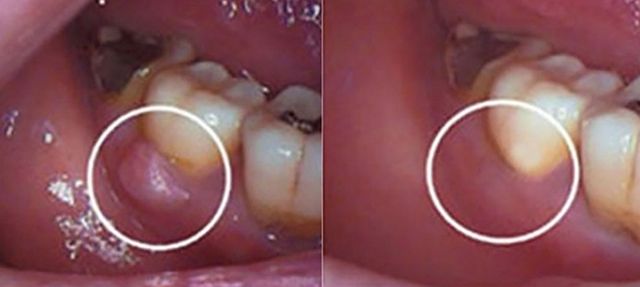

치은염은 증상이 뚜렷하게 나타나지 않아 간단한 치료만으로 회복할 수 있지만, 잇몸이 내려앉아 치아 뿌리가 노출되거나 치주인대와 잇몸뼈가 파괴되는 치주염이 진행되면 이야기가 달라진다.

치주염은 잇몸에서 피가 나고 붓거나 이가 시린 증상이 나타나는데, 이는 만성질환으로 오랫동안 서서히 진행된다. 치주염이 심해지면 건강한 잇몸으로 돌아가기가 사실상 불가능하다. 증상이 있든 없든, 나이가 적든 많든 매일 꾸준한 구강 관리가 중요한 이유다.